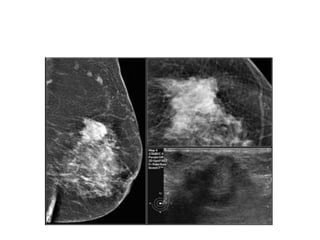

Here a hyperdense mass with an irregular shape and a spiculated margiN.Notice

the focal skin retraction.

This was reported as BI-RADS 5 and proved to be an invasive ductal carcinoma.

Here a hyperdensemass with an irregular shape and a spiculated margiN.Notice the focal skin retraction. This was reported as BI-RADS 5 and proved to be an invasive ductal carcinoma.